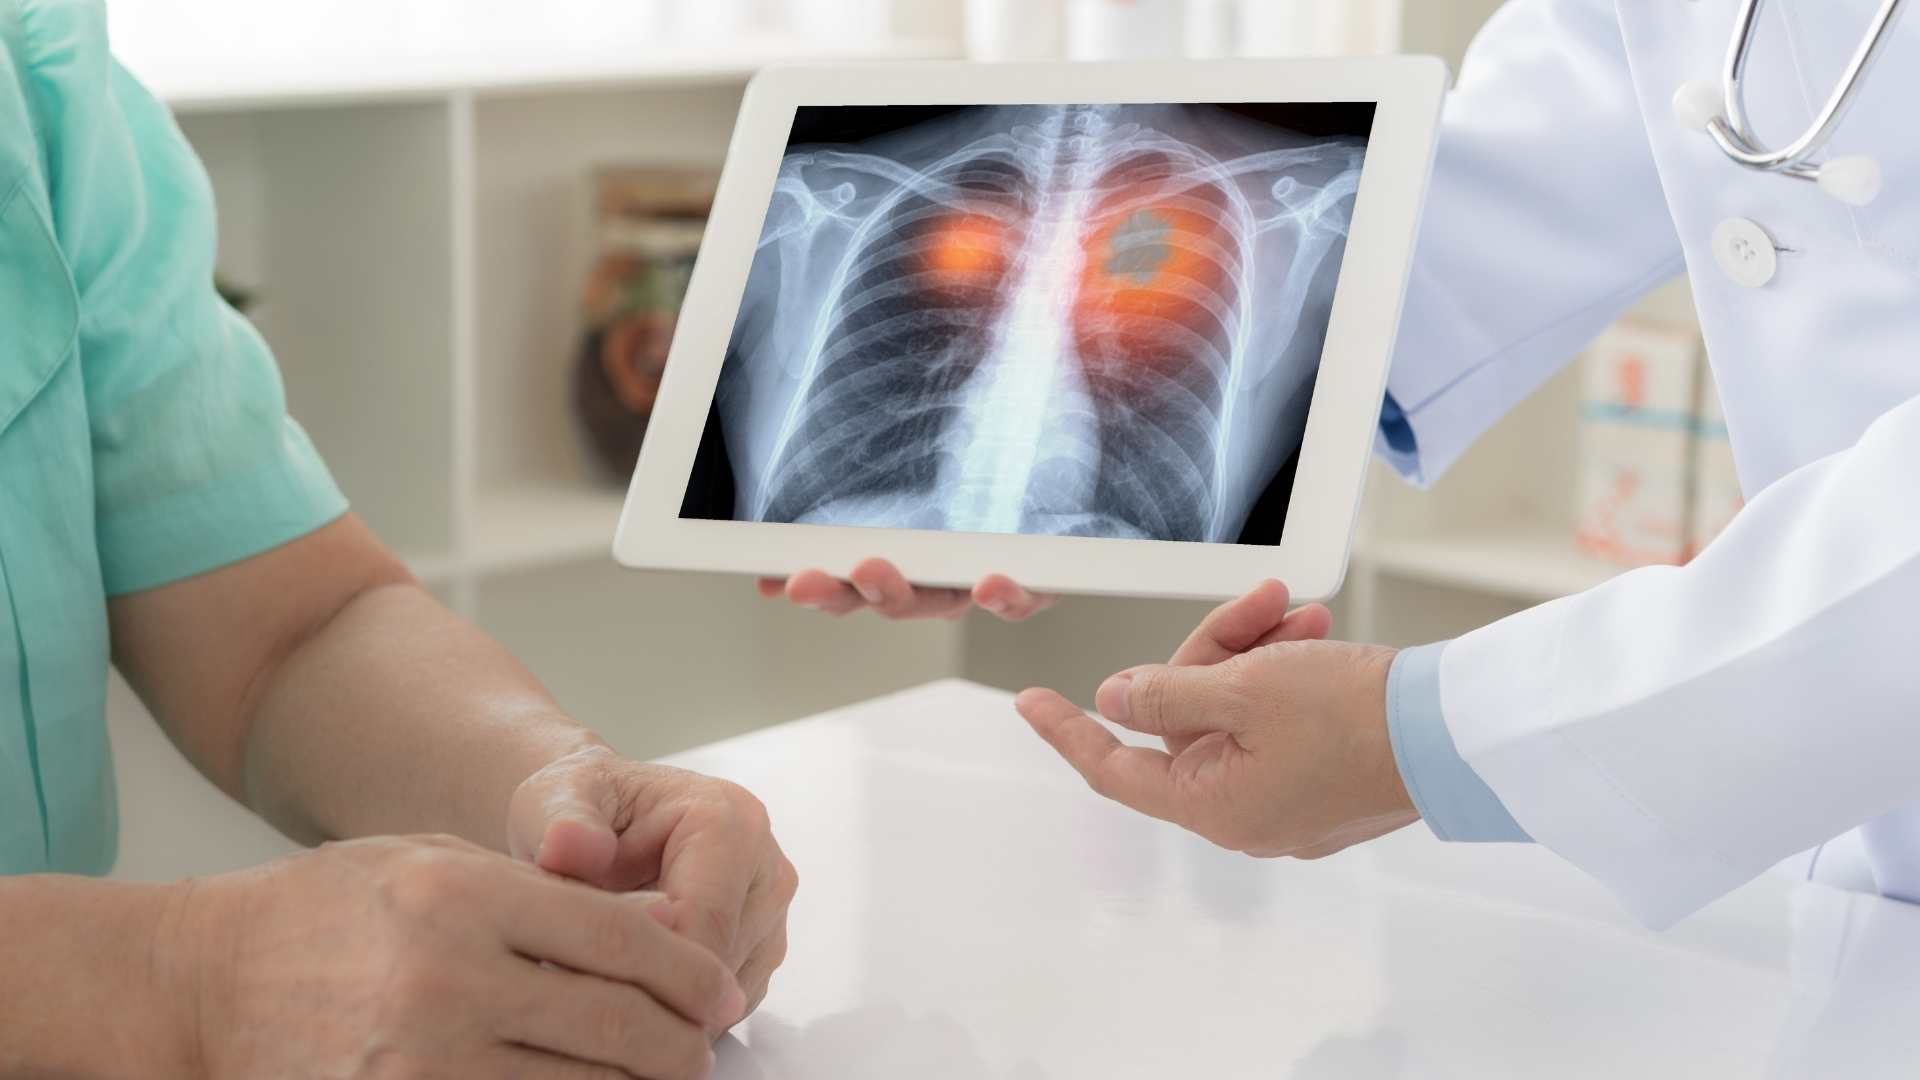

Apakah Kanker Paru-Paru Bisa Sembuh?

Kanker paru-paru adalah salah satu jenis kanker yang paling mematikan karena sering kali tidak terdeteksi sampai stadium lanjut. Pada tahap ini, gejala mulai muncul dan pengobatan menjadi lebih sulit. Namun, dengan deteksi dini dan perawatan yang tepat, peluang pasien untuk menjalani hidup lebih lama dan berkualitas bisa meningkat.

Kesembuhan kanker paru-paru sangat bergantung pada stadium saat diagnosis dilakukan. Pasien yang kanker paru-parunya ditemukan pada stadium awal memiliki peluang kesembuhan yang lebih tinggi karena tumor masih kecil dan dapat diangkat melalui operasi atau kombinasi radioterapi. Stadium awal memungkinkan pengobatan yang lebih efektif dan risiko komplikasi lebih rendah, sehingga pasien bisa kembali beraktivitas lebih cepat.

Semakin awal kanker terdeteksi, peluang sembuh semakin tinggi. Pasien stadium awal biasanya dapat menjalani operasi atau radioterapi yang lebih berhasil. Pemeriksaan rutin sangat penting bagi mereka yang berisiko tinggi. -